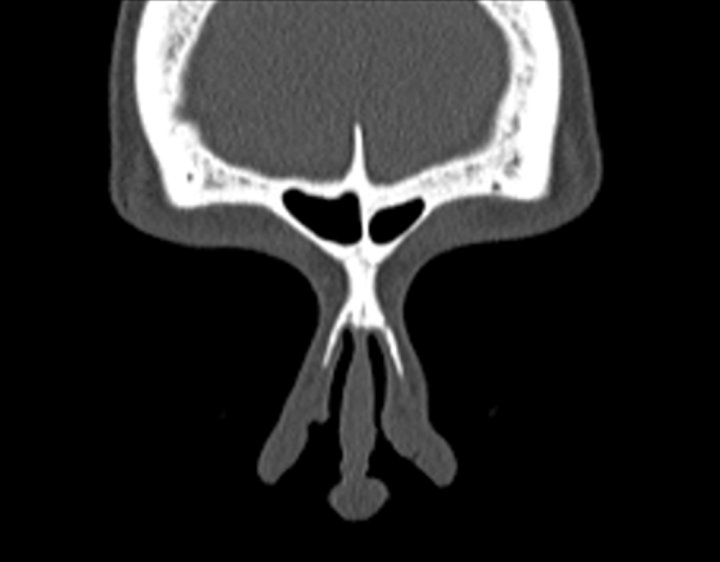

Click any image for labels.